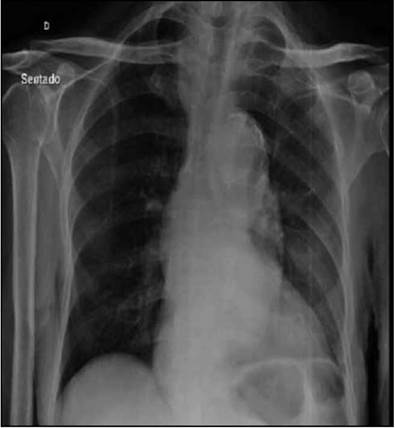

Paciente masculino de 85 años, con cuadro de 12 horas de evolución consistente en dolor torácico opresivo, intensidad moderada, no irradiado, inicio gradual, duración mayor de 30 minutos, asociado a disnea de medianos esfuerzos. Antecedentes personales: HTA, enfermedad renal crónica, insuficiencia cardiaca (FE 22%). Examen físico: normotenso, euvolémico, auscultación cardiaca con soplo sistólico en foco mitral, resto del examen sin alteraciones. Se realiza impresión diagnóstica de síndrome coronario agudo y se solicita electrocardiograma que muestra bradicardia sinusal y hemibloqueo anterior izquierdo; marcadores de necrosis miocárdica negativos y radiografía de tórax con signo del calcio positivo: calcificación del botón aórtico con separación mayor a 1 cm entre la calcificación intimal y el borde externo de los tejidos blandos de la aorta torácica (Figuras 1, 2). Sospechamos síndrome aórtico agudo y solicitamos eco transesofágico, con arco aórtico de difícil visualización, dilatación de la aorta descendente (44 mm), imagen sugestiva de hematoma intramural aórtico. Se realizó an-giotomografía de tórax confirmando hematoma en la aorta torácica descendente. Evaluado por cirugía vascular se opta por tratamiento clínico debido a la edad y comorbilidades.